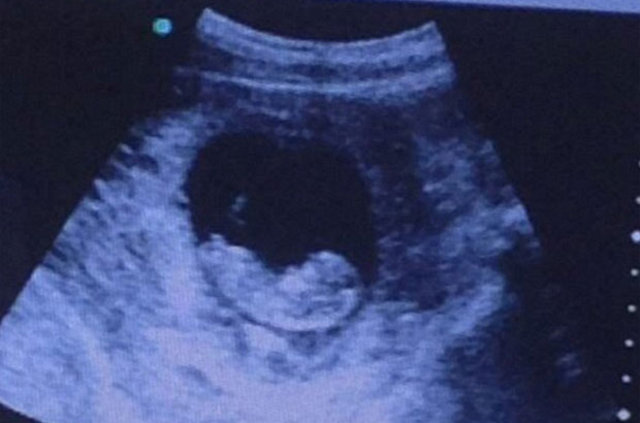

"Luigivampa-over9000" adlı kullanıcı tarafından siteye yüklenen bu fotoğrafta henüz 10 haftalık olduğu tahmin edilen bir bebeğin ultrasonu görülüyor. Bu fotoğrafın fazla ilgi çekmesinin nedeni ise bebeğin sağ tarafında fark edilen "şeytan" görüntüsü...

Binlerce kişinin dikkatini çeken bu kare hakkında "yoğun istek" üzerine bilgi veren "Luigivampa-over9000" "şu anda her şey yolunda ancak doktorlar da bu görüntünün ne olduğunu açıklayamadı" açıklamasında bulundu.

Ultrason görüntüsüne yorum yapan kullanıcılar ise "şeytan 2016'da dünyaya geliyor" şeklinde yorumlar yaptı.